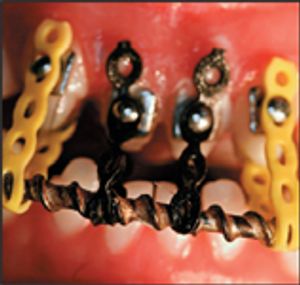

The primary objective of veterinary orthodontics is to provide a comfortable bite for companion animals. Cosmetics are often improved, however orthodontic care is never provided for deceptive purposes. Our ethical priority is to provide genetic counseling to avoid future problems associated with malocclusions. Traumatic malocclusions are painful for pets and painfully expensive for owners.